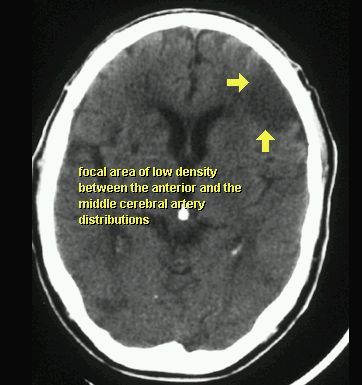

UDAR NIEDOKRWIENNY MÓZGU (ZAWAŁ MÓZGU)

TK